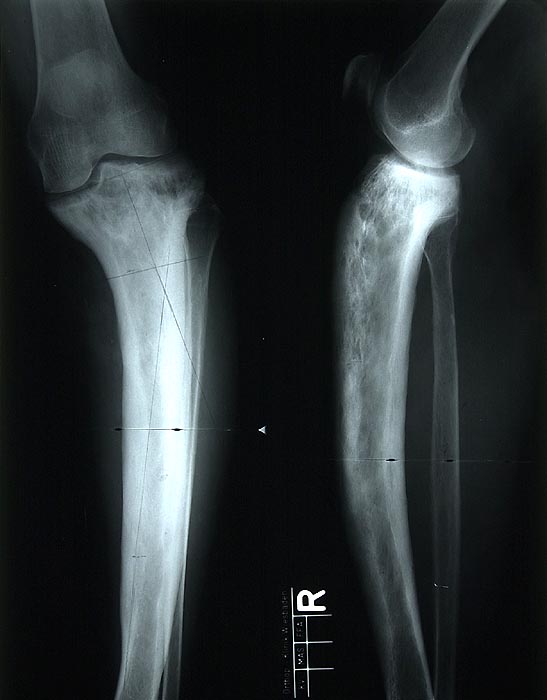

Oft wird die Diagnose als Zufallsbefund in einem Röntgenbild (> 5037) gestellt. Das Röntgenbild zeigt eine erhöhte Knochendichte, eine Verdickung der Corticalis, eine Knochendeformität und eventuell Mikrofrakturen. Die alkalische Phosphatase im Serum ist erhöht, während Kalzium und Phosphatspiegel im Normbereich liegen. Im Urin und im Serum lassen sich erhöhte Hydroxyprolinspiegel nachweisen (Kollagenabbau). Eine Knochenszintigraphie kann als Screeninguntersuchung zur Lokalisierung von Paget Herden verwendet werden.

An den betroffenen Stellen ist sowohl der Knochenabbau als auch der Knochenanbau gesteigert. Die Osteoklasten sind auffallend gross und enthalten sehr viele Kerne (> 3518). Die aktivierten Osteoblasten produzieren verdickte und grob geflochtene Spongiosabälkchen. Der neugebildete Knochen ist strukturell und morphologisch abnorm und schlecht mineralisiert. Der Knochen wird dadurch weich und anfällig auf Frakturen oder Deformation unter Belastung (nach vorne gebogene Säbelscheidentibia). Das Knochenmark wird ersetzt durch fibrovaskuläres lockeres Stroma, welches an Granulationsgewebe erinnert. Mikroskopisch werden eine osteolytische Initialphase, eine Umbauphase mit verstärkter Knochenneubildung und eine sklerosierende Stabilisationsphase mit strukturellem Umbau und Spongiosierung der Kortikalis (verbreiterte spongiosaartige Kortikalis) unterschieden.